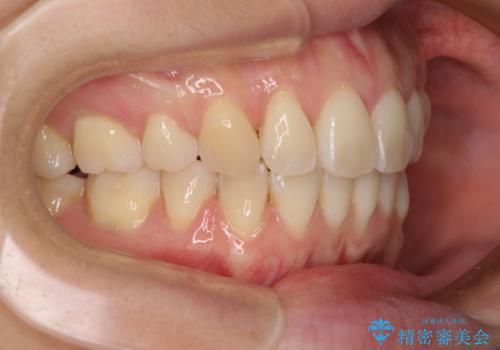

前歯のデコボコを抜歯矯正で改善 メタル装置で費用を抑える

もう少し口元の突出感を改善したかったのですが、舌の突出癖が影響し下顎前歯が唇側に押させる仕上がりとなりました。